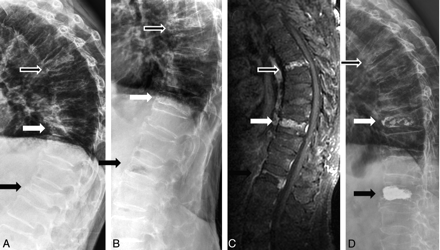

Toyone et al8 used supine and standing radiographs, and McKiernan et al1 used standing and supine (with or without bolster) radiographs to demonstrate mobility. In the study of McKiernan et al, dynamic fracture mobility was demonstrated in only 44% of patients, but they did not use a bolster in supine lateral radiographs in all patients. The vertebral body height is taller in supine with bolster radiographs (Fig 1B, white arrow) than in supine-only radiographs (Fig 1C, white arrow). In the study of McKiernan et al, 23 mobile fractures all showed marked mobility and the average anterior vertebral height increased 106% compared with the initial fracture height.1 No case of mild mobility was noted in their study. However, in another study by McKiernan et al,9 they demonstrated latent mobility of osteoporotic VCFs that was not obvious in their current standing and supine lateral radiographs. This means that mild mobility cannot be demonstrated in standing and supine lateral radiographs. To get the best comparison effect, we modified this technique and used sitting (instead of standing) and supine cross-table with bolster lateral radiographs in every patient. Although 99% of our patients showed dynamic mobility, 24 patients showed only mild mobility (Fig 2, white arrow). The mild mobility in these patients may be not obvious in standing and supine radiographs. If the patients with mildly mobile VCFs are excluded, then the percentage drops to 76.2%.

A 65-year-old woman with severe back pain due to T8 and T10 compression fractures. A and B, Sitting (A) and supine with bolster (B) lateral radiographs show mild mobility at T8 (white arrow) and no mobility at T10 (black arrow). C, Sagittal STIR MR image demonstrates hyperintensity at T8 and T10. D, Postvertebroplasty lateral radiograph shows cement filling in T8 and T10.